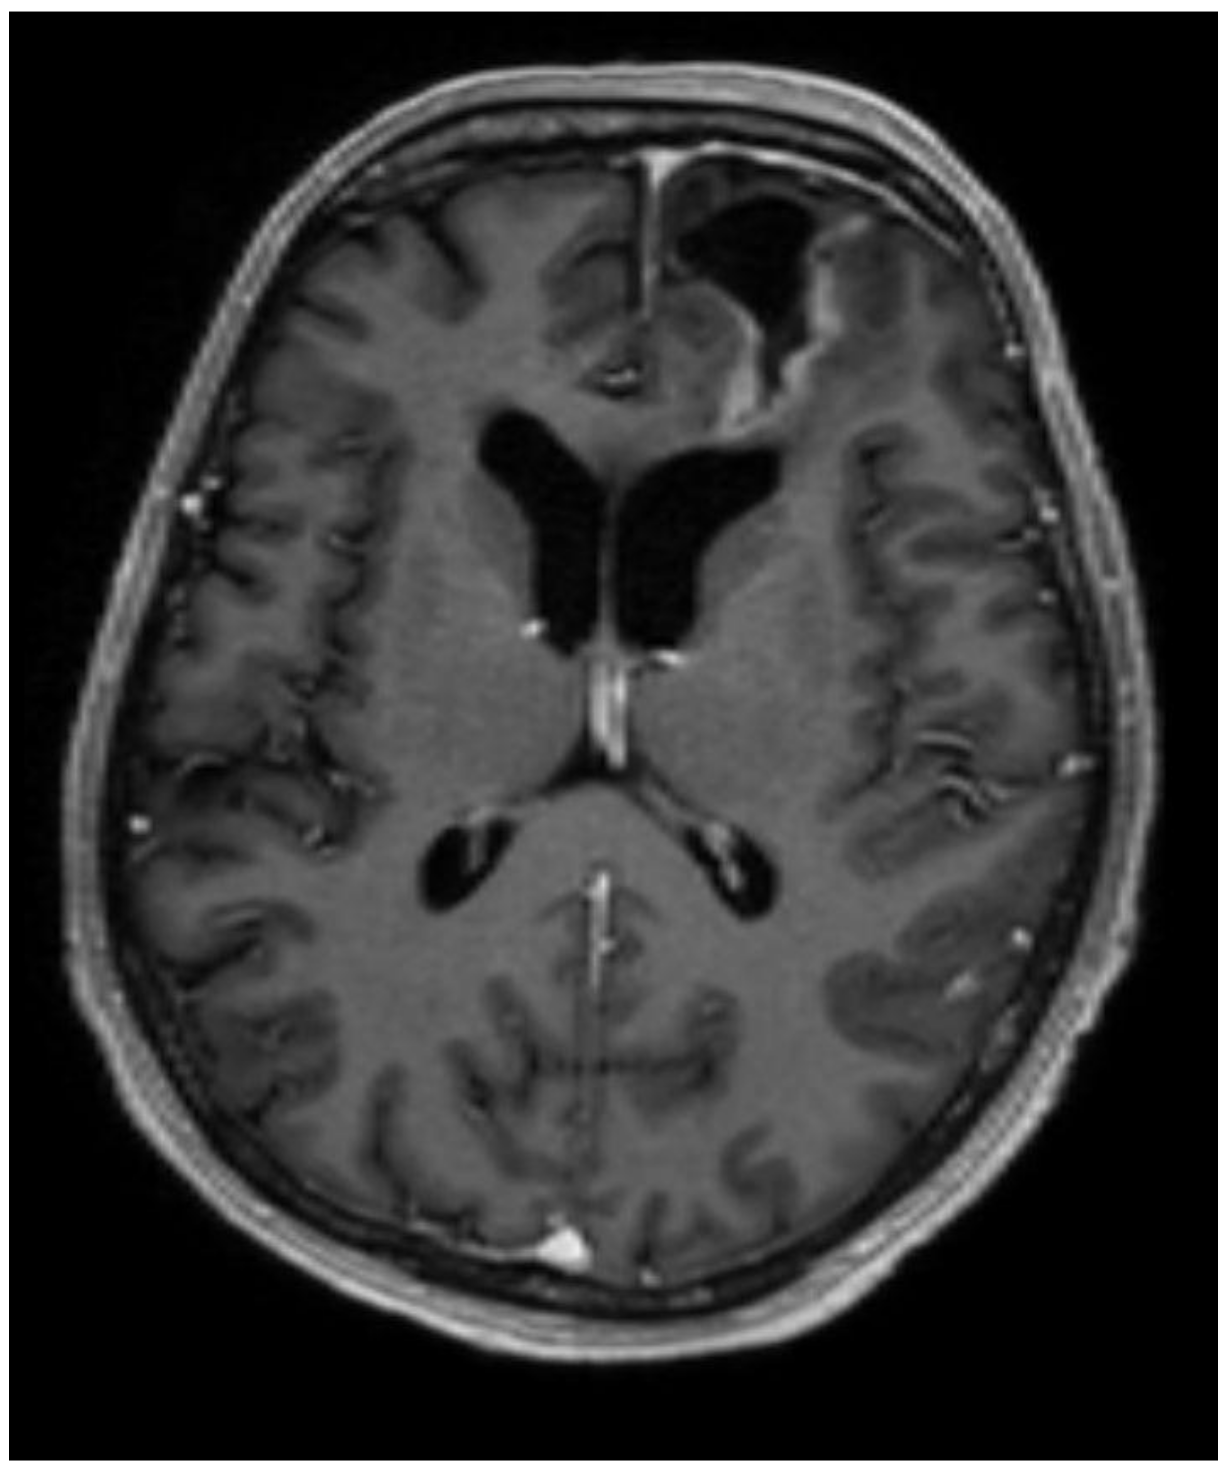

2. Case Presentation